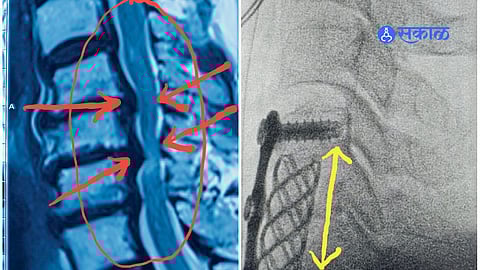

मणका आणि मज्जारजूच्या आजारामध्ये एक असं वैशिष्ट्य आहे, की लक्षणाचं निदान कधी-कधी उशिरा होतं. ‘आजार एका ठिकाणी आणि लक्षणे दुसऱ्याच ठिकाणी’. सर्वच मज्जासंस्थेच्या (Nervous System) बाबतीत तर हे सूत्र खरं आहे. प्रत्यक्ष मेंदूला किंवा मज्जारज्जूला वेदनेची स्वतःची संवेदना नसते. म्हणजेच, शस्त्रक्रिया करताना या महत्त्वाच्या अवयवांना छेद दिला, तर तिथे वेदना होत नाहीत. मात्र, या अवयवांवर आलेला थोडासाही दाब शरीराच्या दूरवरच्या भागात मोठी उलथापालथ घडवून आणतो.